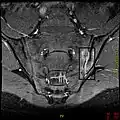

If these criteria still do not give a compelling diagnosis magnetic resonance imaging (MRI) may be useful.[21][23] MRI can show inflammation of the sacroiliac joint.

T1-weighted MRI with fat suppression after administration of gadolinium contrast showing sacroiliitis in a person with ankylosing spondylitis